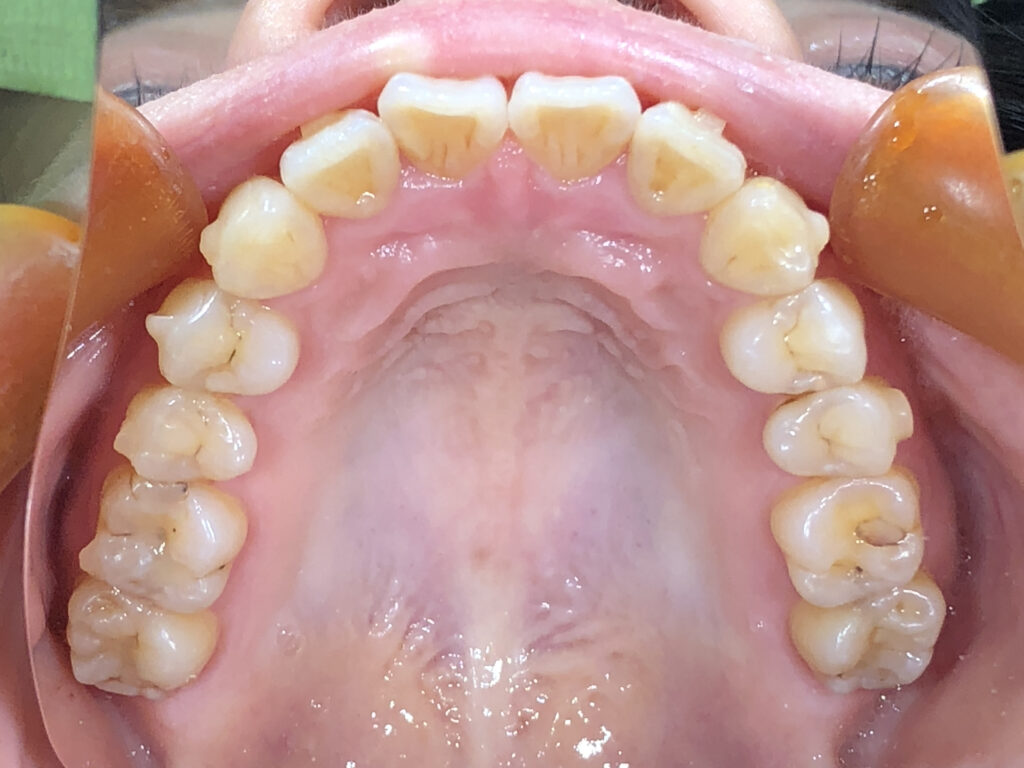

上顎

治療後